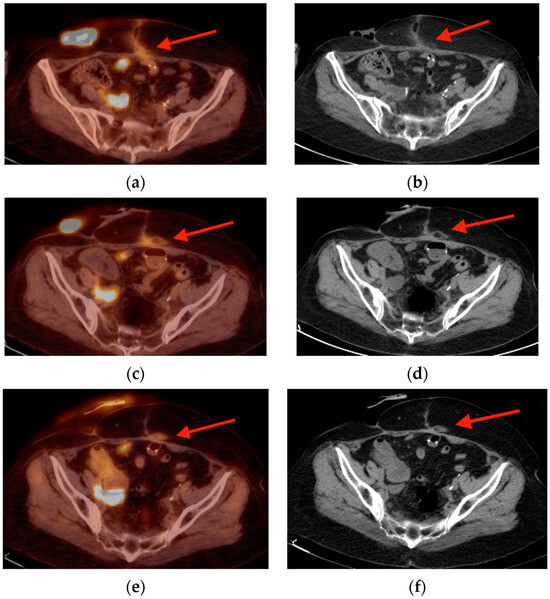

3.1. Enthesopathy

- Resnick, D.; Niwayama, G. Entheses and enthesopathy. Anatomical, pathological, and radiological correlation. Radiology 1983, 146, 1–9. [Google Scholar] [CrossRef]

- Taniguchi, Y.; Arii, K.; Kumon, Y.; Fukumoto, M.; Ohnishi, T.; Horino, T.; Kagawa, T.; Kobayashi, S.; Ogawa, Y.; Terada, Y. Positron emission tomography/computed tomography: A clinical tool for evaluation of enthesitis in patients with spondyloarthritides. Rheumatology 2010, 49, 348–354. [Google Scholar] [CrossRef][Green Version]